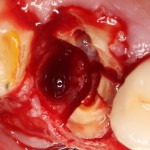

Герметичное ушивание операционной раны или лунок удаленных зубов

В этом состоит едва ли не главное отличие в хирургическом лечении пациентов на антиостеопорозной терапии. Если в нормальных условиях мы обычно оставляем лунки удаленных зубов открытыми «под кровяным сгустком» в надежде на заживление вторичным натяжением, то в случае с бисфосфонатами всё иначе. Инфицирование кровяного сгустка = инфицирование костных стенок лунки — стопроцентный остеонекроз.

Удаление зубов у пациентов, принимающих бисфосфонаты.

Операция заканчивается ревизией лунок, заполнением их специальными препаратами и наложением швов. Операционная рана наглухо ушивается нерезорбируемым монофиламентным шовным материалом.